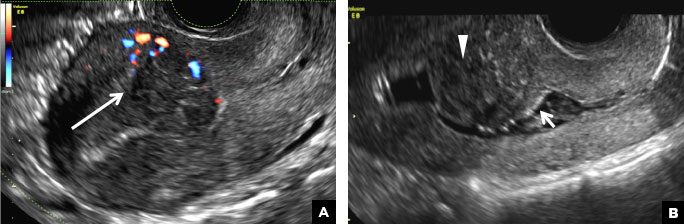

C) Endometrial carcinoma INCORRECT

Endometrial carcinoma on SHG appears as an irregular inhomogeneous lobulated vascular mass distorting the endometrial−myometrial interface.3 Additionally, irregular frond-like projections can be seen extending from the mass into the endometrial cavity, which are distended with echogenic fluid.2

Endometrial carcinoma. (A) Transvaginal pelvic ultrasound demonstrates a retroverted uterus with the endometrial cavity distended by tissue and fluid. An irregular inhomogeneous lobulated mass with frond-like projections (long arrow) distorts the endometrial−myometrial interface (short arrow). (B) Color Doppler image shows marked vascularity within the mass and echogenic fluid in the endometrial canal (arrowhead).